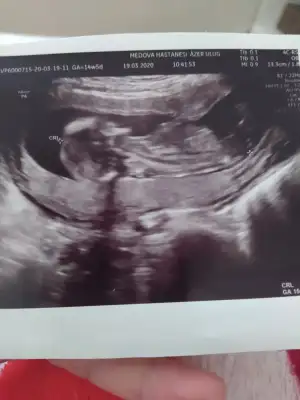

Merhabalar, ctesi ikili test icin gittim 11+6 idim. Suana kadar hep haftayla uyumlu giderdi sat. Ama bu sefer 12+6 cıktım. Yine de cinsiyet yorumlar mısınız? Gec mi kaldım? Bir de doktor tahminini söyledi ama emin değil. Kafanız karışmasın diye en son söyleyeceğim.

Bir de bunu verdi doktor. Sanırım bacak arası ve kenardakiler de bacakları burada. 11+6 idim.